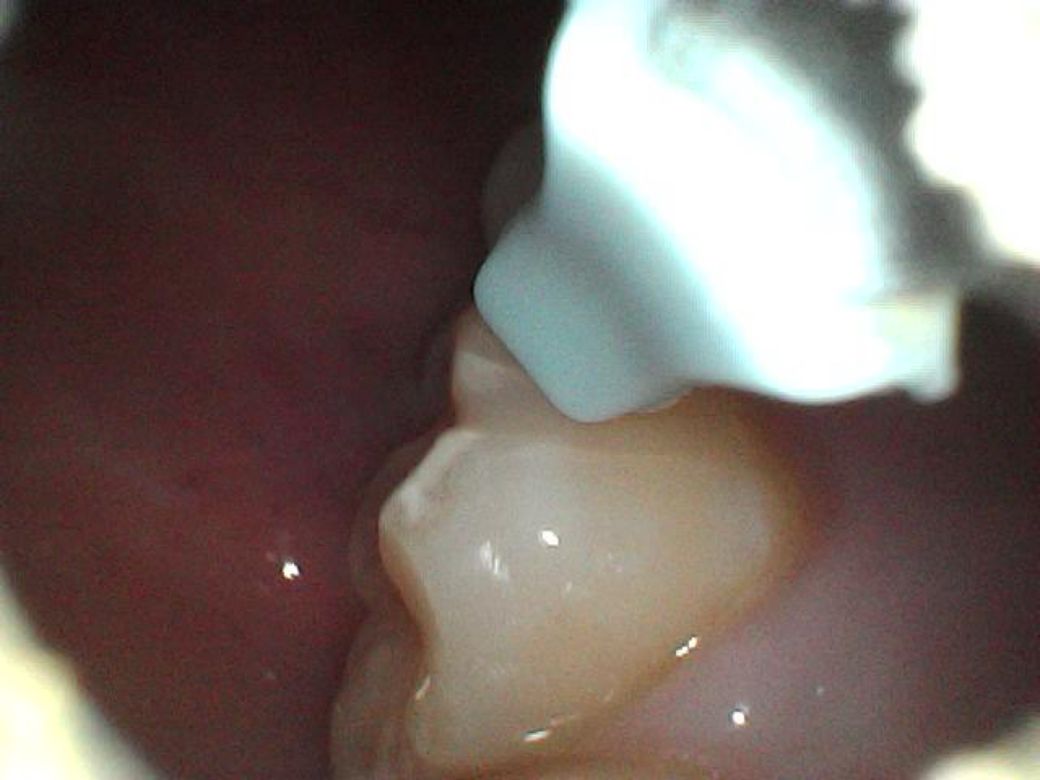

어제 아침, 오늘 아침 이틀동안 찍은 사진들인데 이거 혹시 사진으로 뭔지 구분이 가능할까요?

어제보다 크기가 좀 줄어든 느낌이라 치석인가

싶어 다행은 한데..

명절이라 치과도 안하고 ㅎㅎ..

처음 두장이 어제, 나머지가 오늘 사진입니다

오늘

• 3번 째 사진

• 4번 째 사진

탄산음료등을 자주 마신다면 치아 표면이 탈회되서 그럴가능성도 있습니다. 치과에 가셔서 검진을 받아보세요.

특별히 무엇이 보이지는 않습니다. 크기가 줄어든 것으로 보인다면 충치보다는 치석일것 같습니다.

치아가 발생중인 치배상태에서 외부자극을 받개 되면 표면이 하얗게 형성되는 경우가 있습니다.

크게 문제가 되는 상황은 아닐 가능성이 높지만 자세한 확인을 위해서 치과에서 진료를 받아보세요.

사진만으로 정확히 파악은 어려우나, 현재 초기 충치단계로 보이기에 빠른시일내에 치과에 방문하여 상태를 확인하고 치료를 받길 권합니다.

치석의 형상은 아니고 초기충치 내지는 이전에 떼운재료가 떨어지거나 마모된 것 같습니다 치료가 시급한 정도로의 충치는 아닌것 같습니다